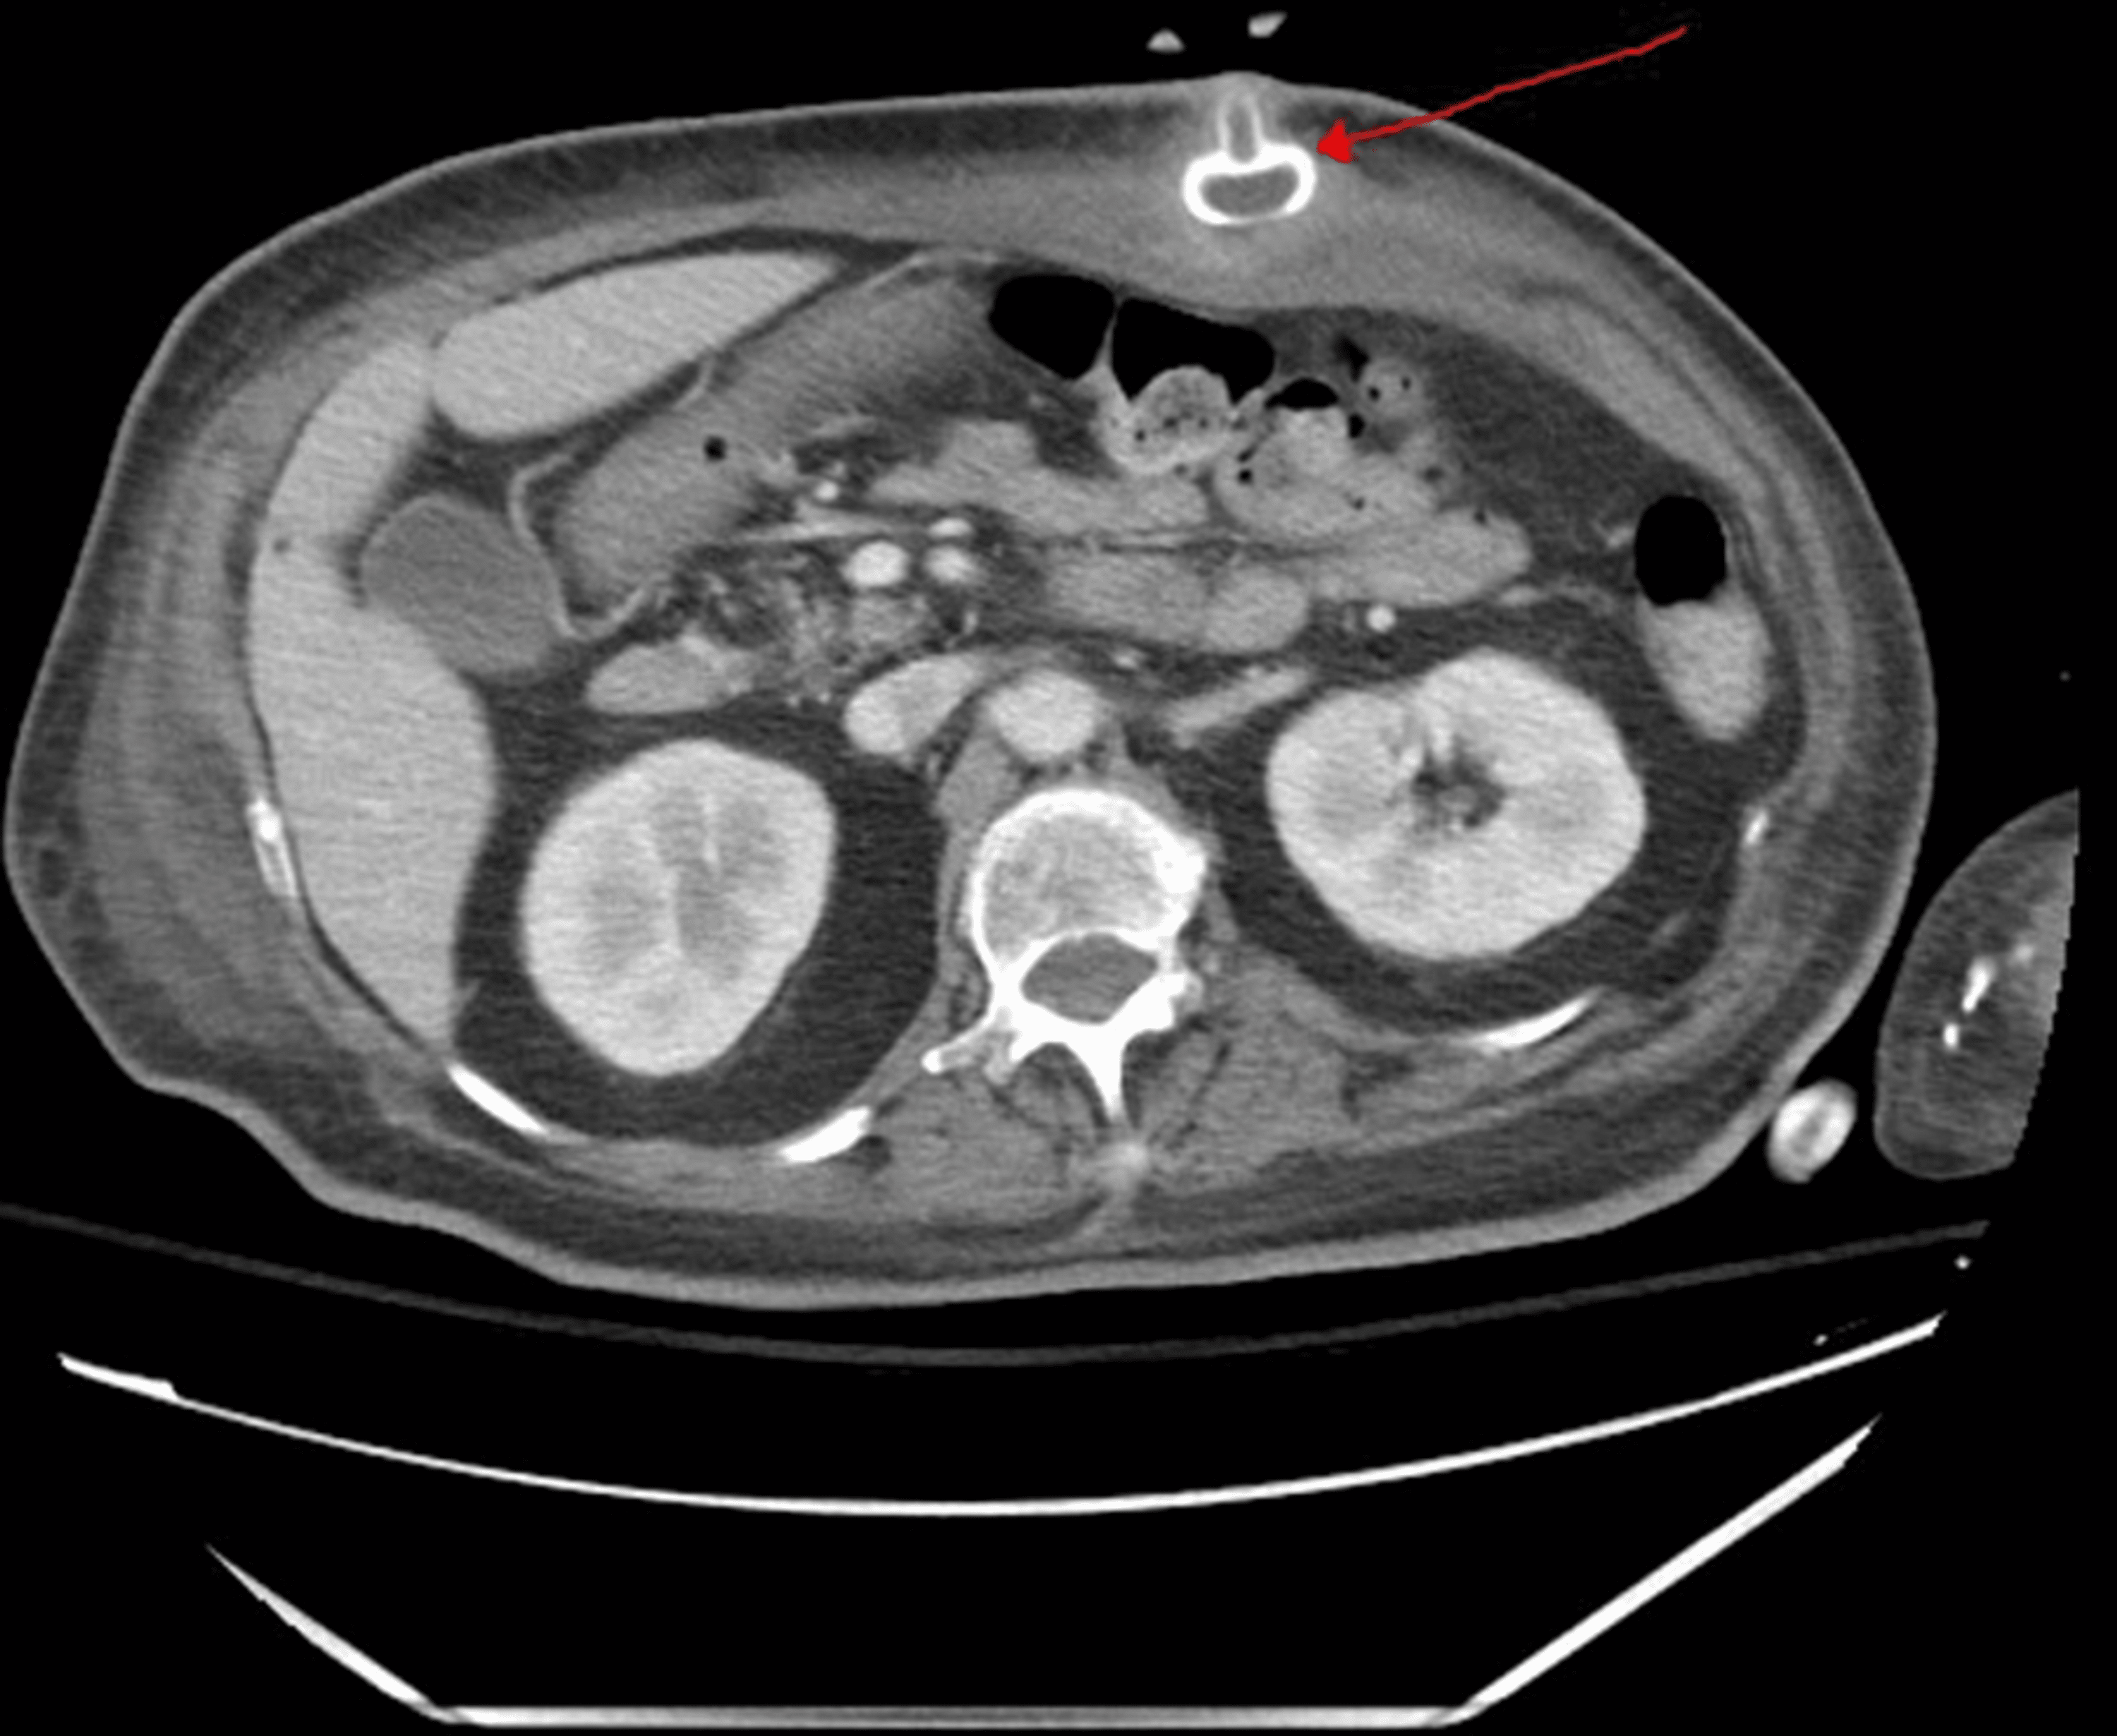

Buried bumper syndrome Image Buried Bumper Syndrome Prevention And Management In The Community buried bumper syndrome (bbs) is a complication of percutaneous endoscopic gastrostomy (peg) feeding with a gastric mucosa shelf over the tube. buried bumper syndrome (bbs) represents a less common but major complication of peg. buried bumper syndrome (bbs) is a rare complication of percutaneous endoscopic gastrostomy (peg) tubes. a buried bumper syndrome (bbs) means that the. Buried Bumper Syndrome Prevention And Management In The Community.